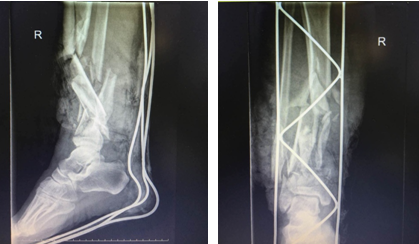

患者右小腿創(chuàng)傷部位CT照片

第一步:2017年12月16日,入院當(dāng)天,患者在氣管插管全麻醉下行右小腿清創(chuàng),對其壞死潰爛的皮膚進(jìn)行清理,進(jìn)行脛前動脈吻合,對骨折的部位進(jìn)行固定,并在患者的創(chuàng)傷部位行VSD負(fù)壓吸引術(shù)(具有清創(chuàng)、止血、吸附壞死組織細(xì)胞、促進(jìn)肌肉組織生長等功效)。手術(shù)從當(dāng)天晚上8:00多進(jìn)行到次日凌晨2:00左右,多名醫(yī)護(hù)人員在手術(shù)臺上連續(xù)奮戰(zhàn)6個小時左右。

清創(chuàng)、骨折部位固定